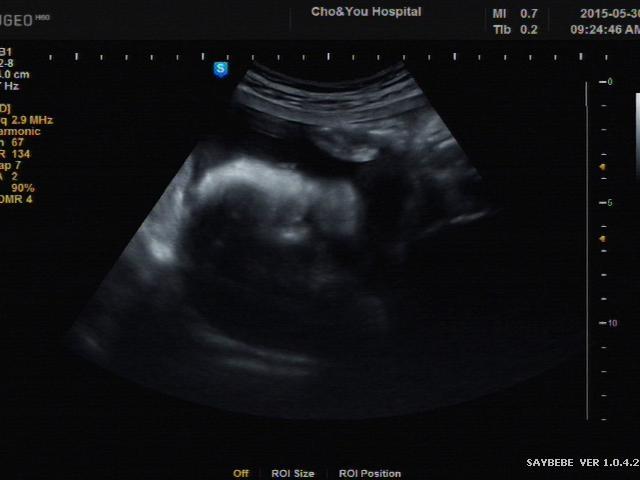

다행히 아기의 심장은 여전히 규칙적으로 뛰고있었다. 자궁이 팽창되며 터졌던 미세혈관에서 고인 피가 한꺼번에 떨어져 나온거라 말했다.

나는 더이상 임신 소식을 미룰 수 없다는걸 알았다. 주렁주렁 뱀처럼 길게 이어붙은 초음파 사진을 안주머니에 꼬옥 챙겨넣고 회사로 돌아왔다.

뭔가 싶겠지만 엄마는 알아볼 수 있는 뚜렷한 두상의 형체. 작은 귀와 눈동자, 아빠를 닮은 하관.